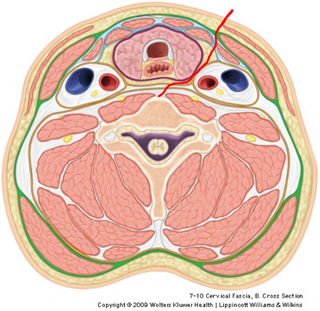

Since all surgery involves damage to the body, the plan is to get to the anterior surface of the vertebral bodies while doing the least damage to nerves, vessels, and visceral structures. As you can see on the image, a route medial to the sternocleidomastoid muscle and the carotid sheath, but lateral to the neck viscera will avoid major damage. Obviously, the strap muscles and especially their innervation from ansa cervicalis may take a severe beating.